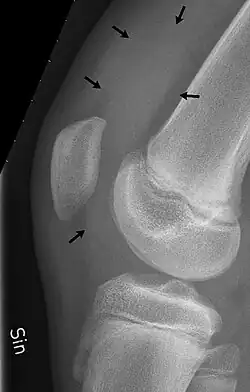

Radiografia do joelho de um menino de 12 anos, com derrame no joelho estendendo-se para a bolsa suprapatelar

1. a bursa suprapatelar ou recesso entre a superfície anterior da parte inferior do fêmur e a superfície profunda do quadríceps femoral.[2] Ela permite o movimento do tendão do quadríceps sobre a extremidade distal do fêmur. Em cerca de 85% dos indivíduos, essa bursa se comunica com a articulação do joelho. A distensão desta bursa é geralmente uma indicação de derrame no joelho .[3]